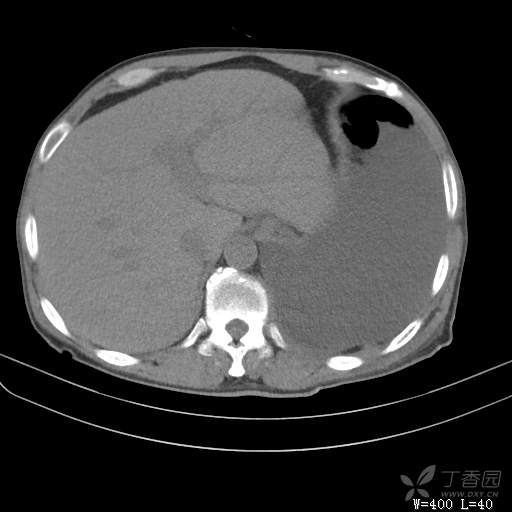

辅助检查:白细胞数目4.41 × 10^9/L,中性粒细胞百分比82.1%,*血红蛋白111g/L,*血小板数目91 × 10^9/L,凝血四项:凝血酶原时间12.5秒,国际标准化比值1.07,活化部分凝血酶原时间36.1秒,纤维蛋白原浓度6.52g/L,肾功能示:肌酐47.4umol/L,尿酸150umol/L,电解质示:钠133.5mmol/L,D-二聚体0.88mg/L,血沉67.71MM/H,C-反应蛋白114.6mg/L,肝功能:*总蛋白49.6g/L,*白蛋白27.4g/L,查胸水常规及胸水生化提示渗出液,胸水ADA154U/L,查胸水病理未见肿瘤细胞。超声:腹膜后有3~4枚肿大淋巴结,直径1~1.5厘米,余浅表淋巴结不大。

治疗经过:胸水引流。胸水白蛋白23.8克/升,乳酸脱氢酶275单位/升,胸苷激酶182单位/升,胸水外观黄色混浊,总细胞4320个/微升,白细胞4320个/微升,单核细胞80%,多核细胞20%。考虑结核性胸膜炎,结果查肿瘤标志物、胸水细胞学阴性,胸水TB—DNA阴性,结核菌素试验+,结核抗体阴性,TB-SPOT阴性,胸膜活检阴性。怎么办?